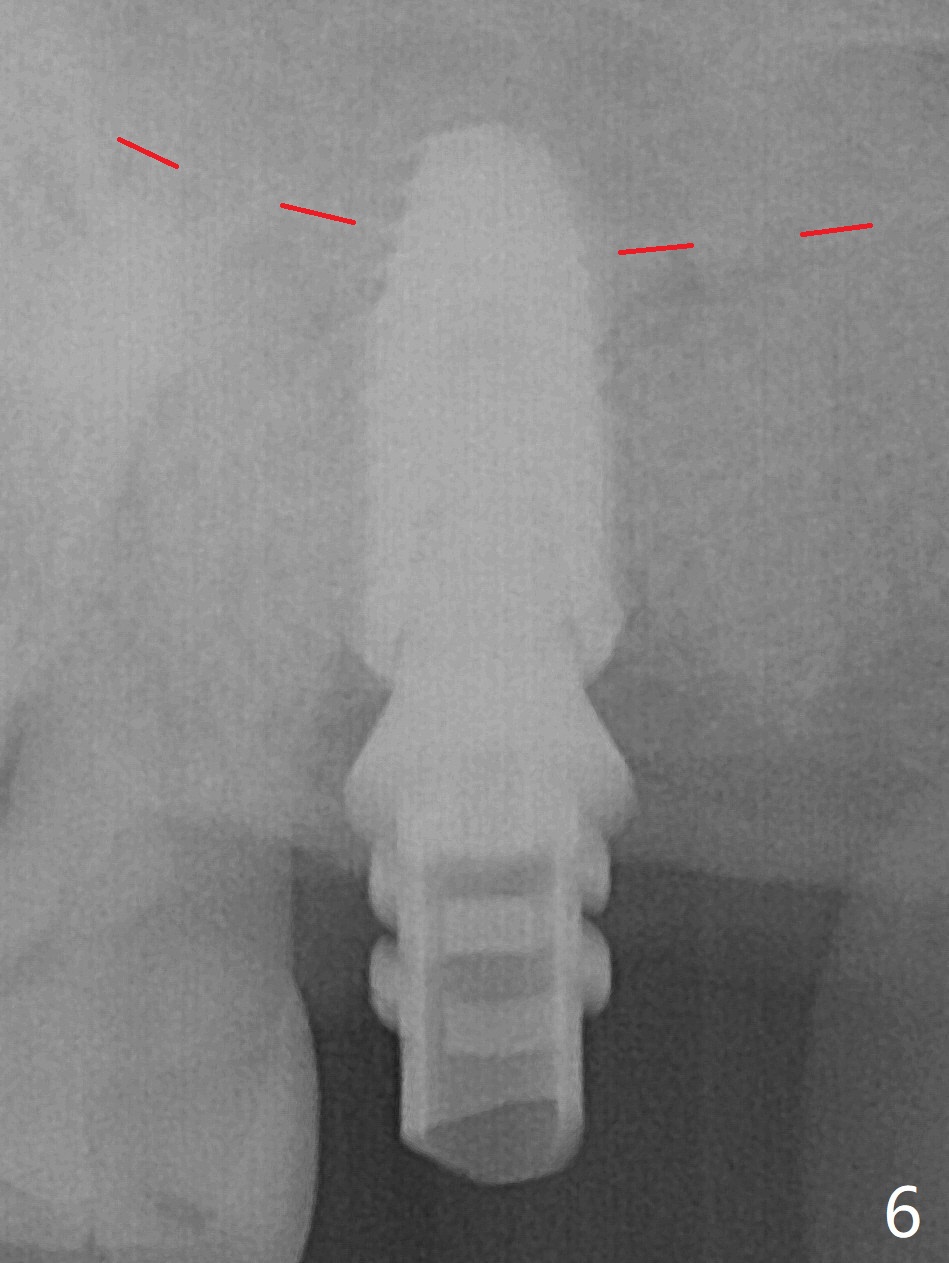

Although the buccal (Fig.1 (mesial view of the extracted tooth #15): B) root is larger than the palatal (P) one, the palatal socket is larger than the buccal one (Fig.2 white area) because of the bone loss of the former. For better restoration, osteotomy (Fig.2 red line) is initiated in the buccal slope of the septum (S) so that the final osteotomy is in the middle of the whole socket (Fig.3 red box). In fact a 3 mm stopper is not used because of the slope and the clumsy stopper. Stopper would be indicated if the bottom of the bone were flat. At first a 4x10 mm dummy implant is placed with stability (Fig.4). After further osteotomy and sinus lift (Fig.6 red dashed line: sinus floor), a 5x10 mm implant is placed with 30 Ncm, followed by insertion of a 5.2x8(2) mm temporary abutment (Fig.5,6). The latter holds an immediate provisional and Vanilla Graft/Osteogen (Fig.7 *) in place (^: distal crestal bone). Although the bone looks normal around the implant 7.5 months postop (Fig.4), the implant is unstable, probably due to the large preexisting defect. In contrast the implant placed at the healed site of #3 is stable 6.5 months postop. The 8x5 mm healing abutment that dislodged for 1 day could not return. A 6x5 mm one is used; it appears that the bone density mesial and distal to the implant is low (Fig.9 *). The implant looks normal and is stable 13 months postop (Fig.10). A 5.7x5.5(5) mm cementation abutment is placed for a provisional (progressive loading, Fig.11). There is no pain associated with the provisional for mastication. Impression is taken 7 days later. The patient has pain when the permanent crown is cemented. It appears that the implant does not osteointegrate and should be removed. A 6x14 mm tissue-level implant will be immediately placed following a 5 and 6x14 mm taps and bone graft and PRF (Metronidazole). In fact there is no pain when the existing abutment is torqued at 35 Ncm 1 year 8 months postop (Fig.12). The mesiogingival portion of final restoration (Fig.13 arrowheads) should be bulky so that the gingival embrasure (red dashed line) is minimal to reduce food impaction.